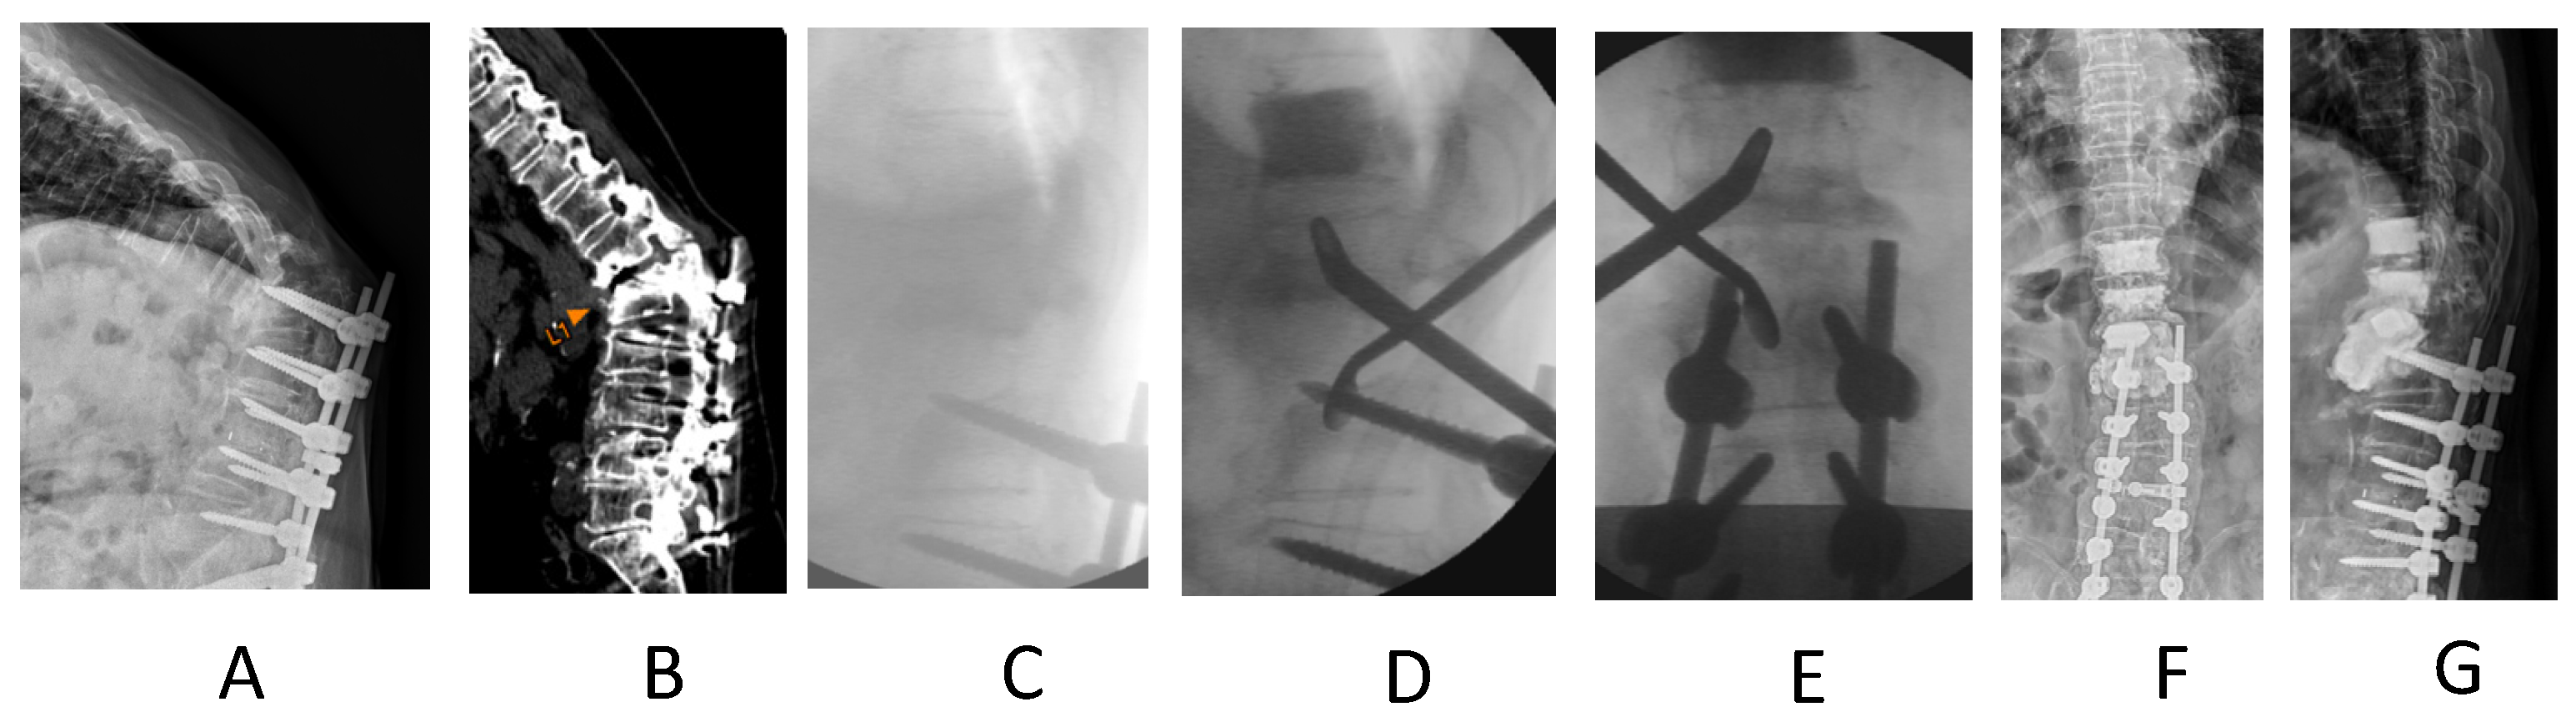

Manual Reduction for Subacute Osteoporotic Burst and Severe Compression Thoracolumbar Fractures

2. Materials and Methods

3. Results